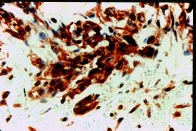

Immunohistochemistry (Formalin/PFA-fixed paraffin-embedded sections) - Anti-VEGF Receptor 1 antibody (AB2350)

ab2350 - immunohistochemistry

Formalin fixed paraffin embedded human angiosarcoma stained with VEGF Receptor 1, using ABC and AEC chromogen.